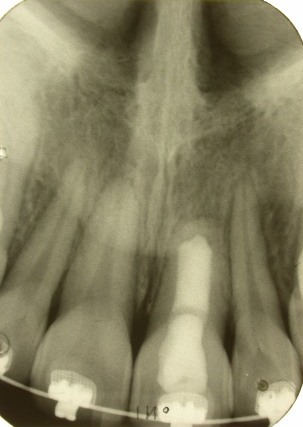

Als er sprake is van een grote apicale lucentie die al langdurig aanwezig is, dan zit er in het periapicale gebied veel granulatieweefsel en is er geen botbarrière.

De barrière kan gemaakt worden door

calciumsulfaat (BoneGen)

in het periapicale gebied aan te brengen. Met behulp van een

MTA GunSystem

wordt calciumsulfaat in het kanaal gebracht. Met handpluggers, ingesteld op de lengte van het betreffende element, wordt de calciumsulfaat voorbij de apex gecondenseerd. Enkele minuten later is het hard geworden. De restjes calciumsulfaat in het kanaal worden verwijderd. Bijvoorbeeld zoals normaal een kanaal wordt gereinigd. Een dikke vijl omwikkeld met watten en daarna vochtig gemaakt is een andere goede methode om de kanaalwand te reinigen. Ook handig is het om te reinigen met behulp van